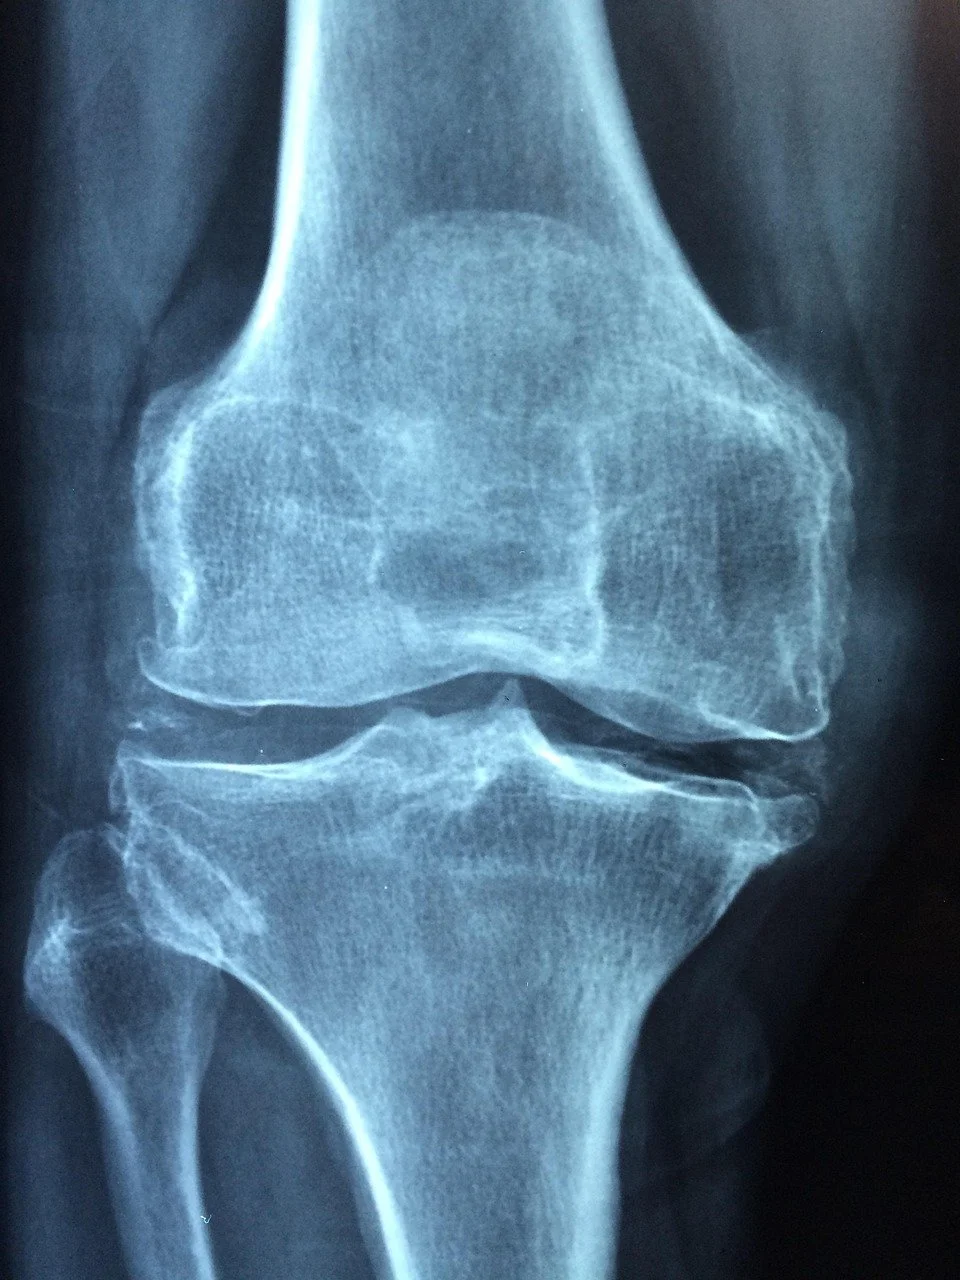

Anyone in chronic pain.  Anyone with arthritis.  Anyone who has been told they are bone-on-bone and need joint replacement surgery.  Anyone with an athletic injury like a sprain or strain.  Anyone who has had joint replacement surgery and is still not back to activity without pain.  Anyone who has had ANY surgery and is still not back to activity without pain.  Anyone who has had a stroke.  Anyone who has a neurological disease.  Anyone who has been told they need spinal fusion surgery.  Anyone who has a limited range of motion.  Anyone who has an ACL-MCL-PCL-LCL-Meniscus tear.  Anyone who has a concussion.  Anyone who has been told they need surgery.